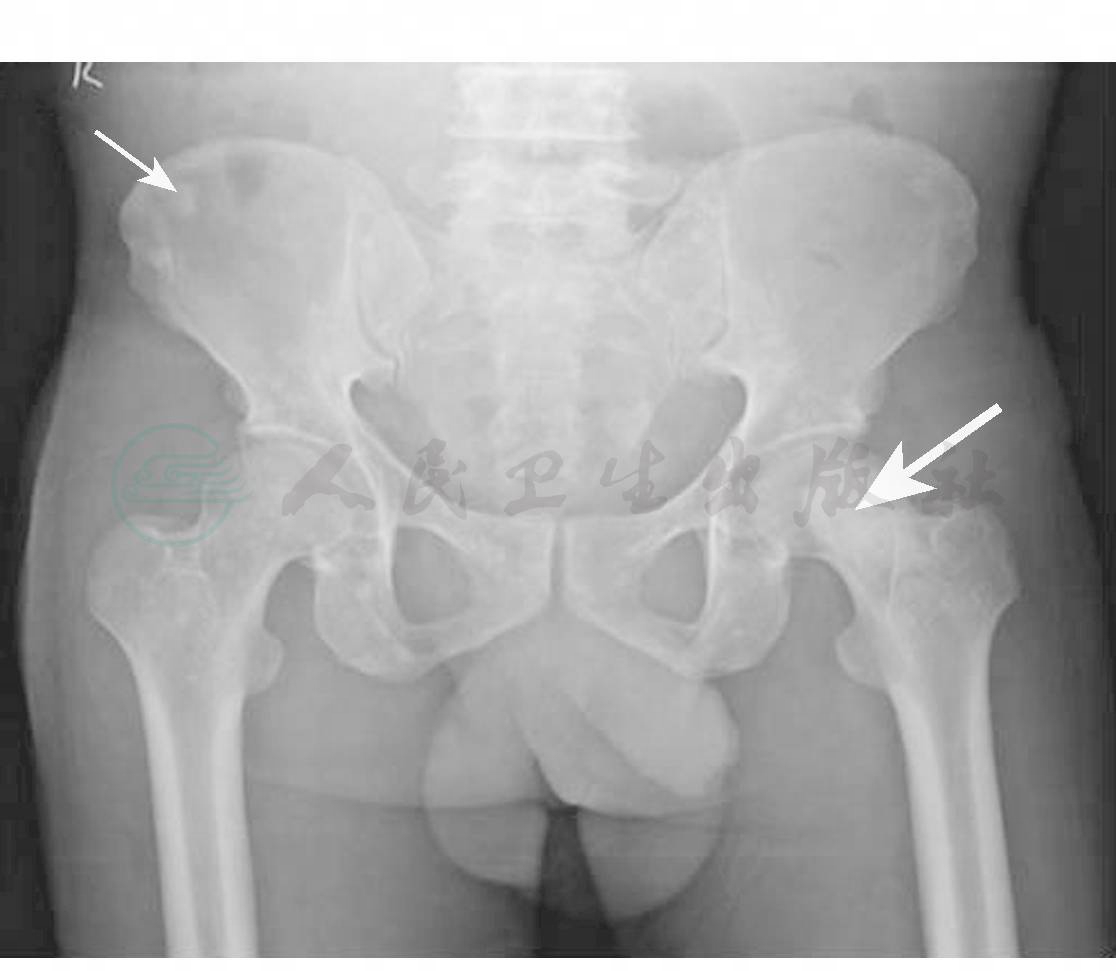

血清免疫固定电泳中可发现特征性单克隆M蛋白,多为IgG或IgA-λ型轻链。脑脊液蛋白水平几乎均升高,常大于1g/L,内分泌检查存在异常。骨髓穿刺浆细胞<5%。骨X线检查有助于发现增殖性骨损害(图3)。骨硬化部位的活检可见恶性浆细胞。肌电图检查示混合性轴索变性和脱髓鞘损害。

图3 骨盆X线

右髂嵴的多发性硬化灶(细箭头)和左侧股骨颈的一个巨大骨硬化灶(粗箭头)